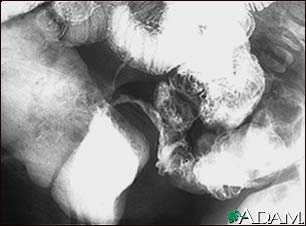

Crohn's disease, X-ray

This lower abdominal x-ray shows narrowing (stenosis) of the end of the small intestine (ileum), caused by Crohn's disease. Crohn's disease typically affects the small intestine, whereas ulcerative colitis typically affects the large intestine. A solution containing a dye (barium), was swallowed by the patient. When it passed into the small intestines, this x-ray was taken (lower GI series).